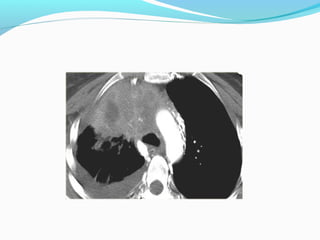

PANCOAST TUMOR

OPERABLE OR NOT?